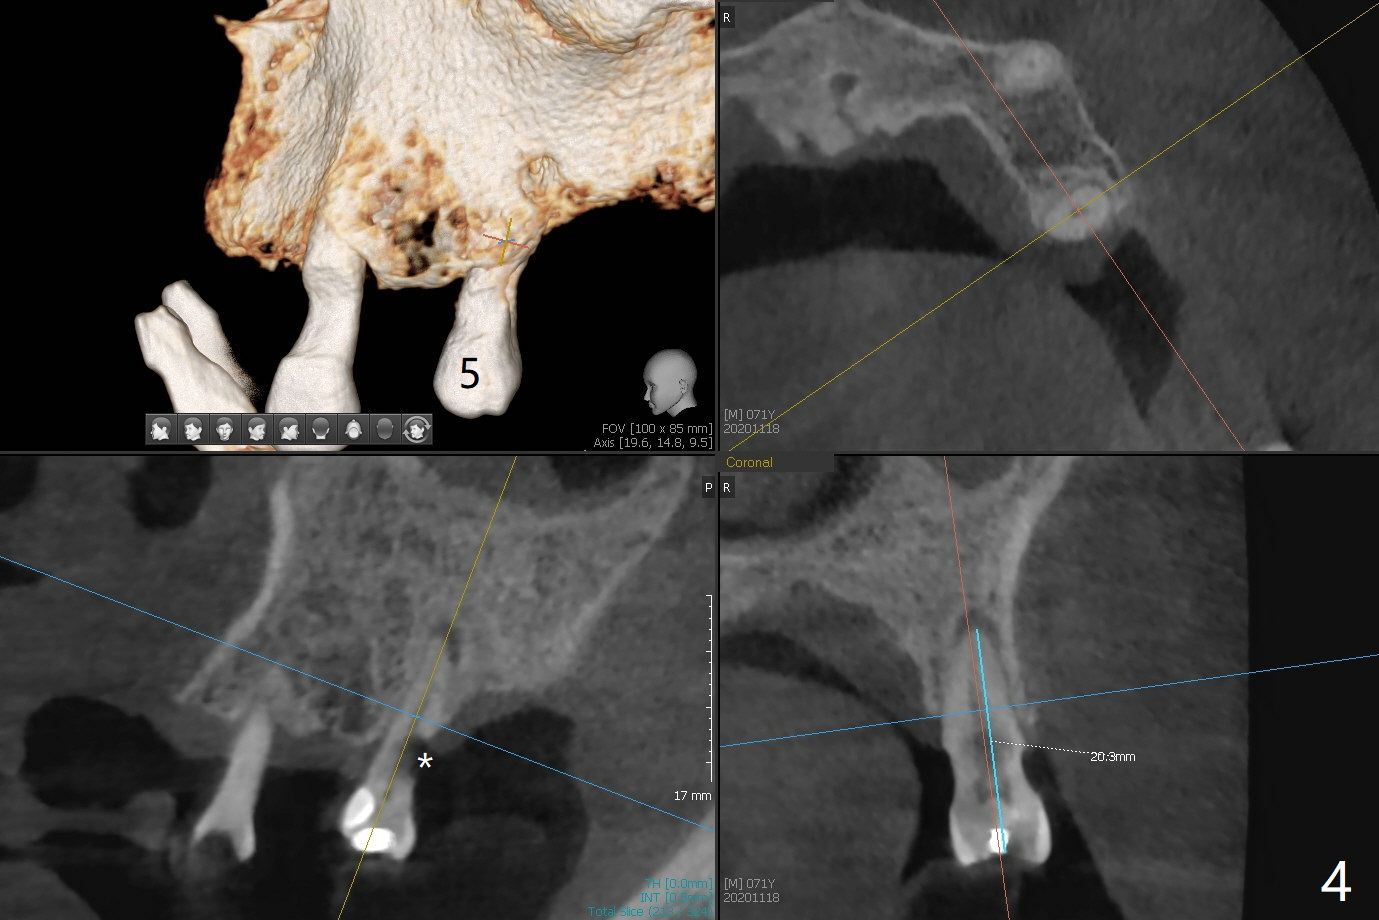

71岁男主诉下颌局部托牙松动(图一),侧切牙不适,临床检查显示后者有咬合创伤,局部卫生不佳,对策:洗牙以及左下4,6植入植体,放置带有球的基台(图五,六)。上颌局部托牙有三个自然牙,挺稳定,但是颈部缺损严重,需要修补(图二,三),左上5远中龋齿需要根管治疗(图四),尽量延长基牙寿命。一个月后病人回来却要求处理松动疼痛右下2,不愿意种植,与3固定和调整咬合,症状消失。Return to No Caries Overdentures Xin Wei, DDS, PhD, MS 1st edition 11/18/2020, last revision 12/13/2020